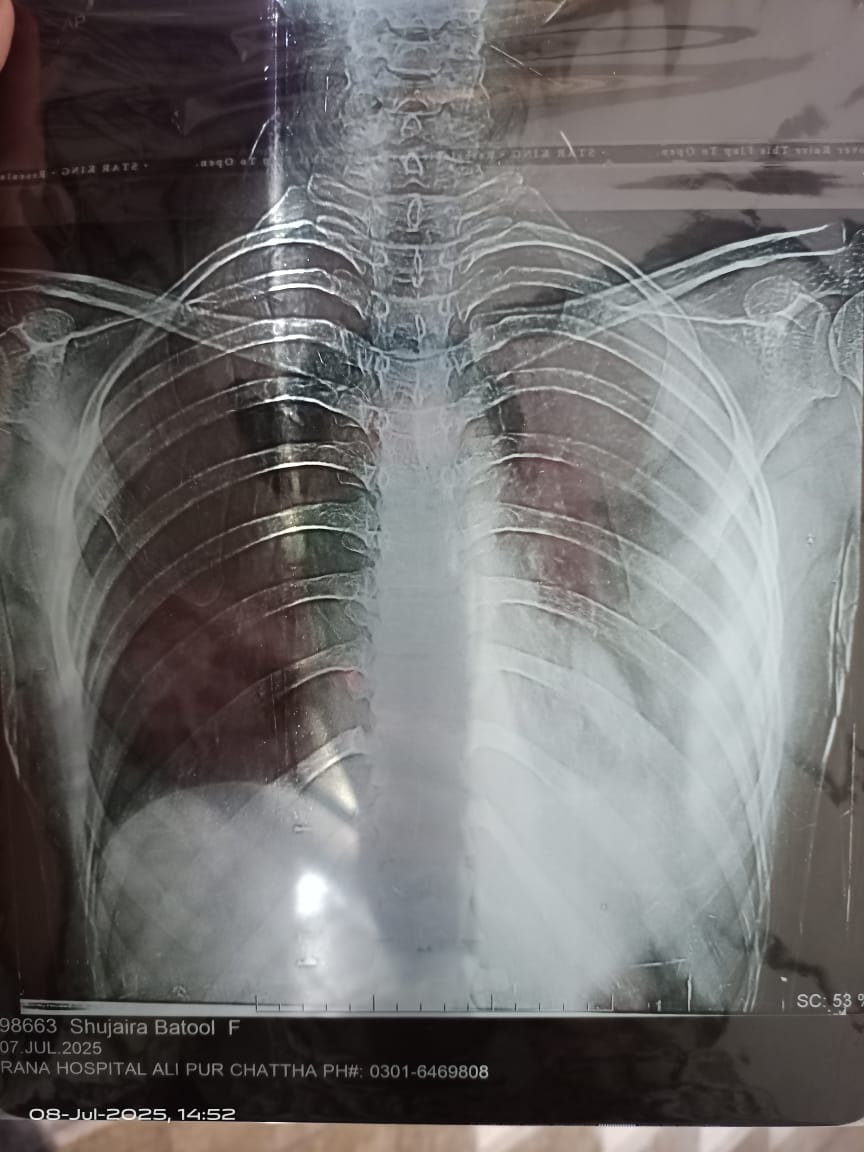

Left sided Pleural Effusion hai.

There is fluid around left lung which is called Pleural Effusion. Fluid should be tested to find the cause

fluid in left lung

needs to find the cause

left side effusion. take consultation from a pulmonologist urgently

left side pleural effusion need to aspiration for diagnostic, take appointment

left side effusion need in clinic appointment for further management